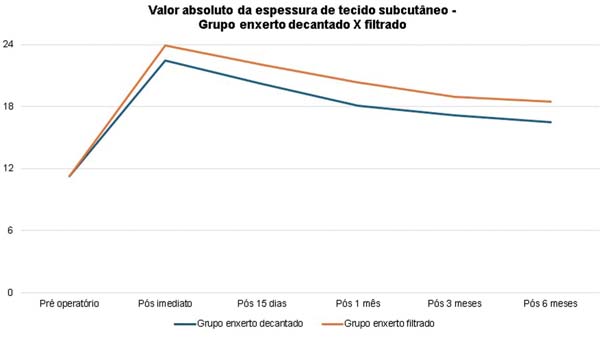

O volume médio de gordura enxertada foi de 116,7 mL no grupo de enxerto decantado e 123,3 mL no grupo de enxerto filtrado. A espessura média inicial do tecido subcutâneo era de aproximadamente 11 mm em ambos os grupos, aumentando para 22 mm no pós-operatório imediato no grupo decantado e 23 mm no grupo filtrado.

Houve reabsorção progressiva em ambos os grupos. A evolução da espessura subcutânea média em ambos os grupos está descrita na ►Tabela 1 e na ►Fig. 5.

No grupo enxerto decantado, a reducãomédia, comparando-se a espessura inicial apos lipoenxertia, foi de 9,90% no 15° dia, 19,27% no 1° mes, 23,59% no 3° mes e 26,36% no 6° mes. No grupo enxerto filtrado, a reducao media, comparando-se a espessura inicial apos lipoenxertia, foi de 7,74% no 15° dia, 14,85% no 1° mes, 20,67% no 3° mes e 22,80% no 6° mes. ►Fig. 6. A evolução ao ultrassom da espessura do tecido subcutâneo antes e depois da lipoenxertia pode ser vista nas ►Figs. 7-8. Os resultados de pré-e pós-operatório de uma paciente de cada um dos grupos estão exibidos nas ►Figs. 9-10.

A comparacao da reducao da espessura subcutanea em 6 meses entre as te cnicas de decantai; a o e filtrai; a o do enxerto na o mostrou diferenc a estatística significativa (p = 0,59).